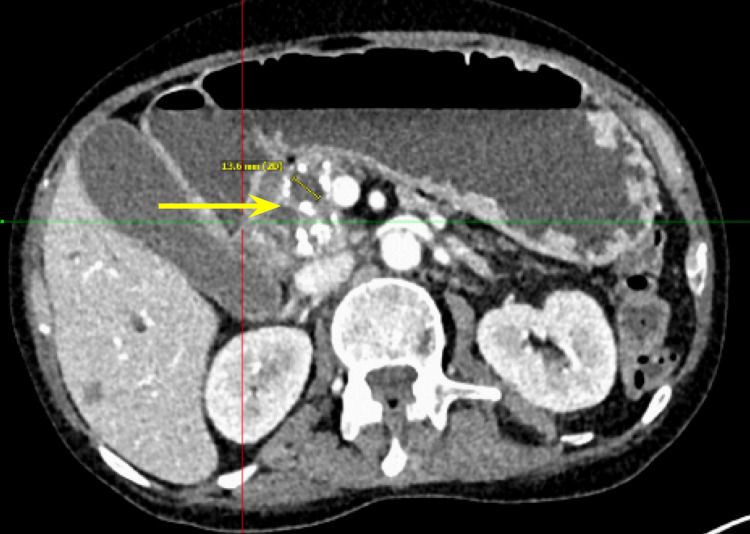

Additionally, there were multiple coarse calcifications throughout the pancreas, consistent with CP (Figure 3). Lastly, the mass was causing significant dilation of the pancreatic (Figure 4), intrahepatic, and extrahepatic biliary ducts.